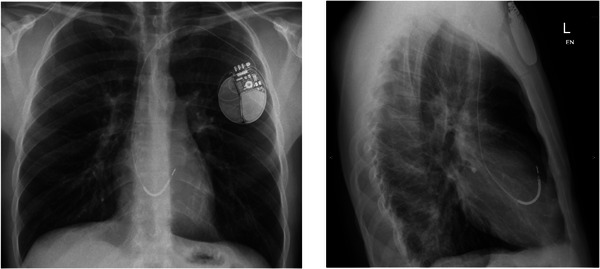

Introduction: Right bundle branch block (RBBB) following cardiac device extraction has not been previously reported but may have catastrophic consequences.

Methods and results: We present two cases of young male patients who developed RBBB following the extraction of single chamber TV ICD systems where the coil was adherent close to the superior tricuspid valve annulus. Both patients had a subcutaneous ICD (SICD) implanted but suffered an inappropriate shock due to T-wave oversensing, requiring very early SICD removal for one patient.

Conclusion: The development of RBBB following the extraction of a TV ICD is a previously unreported complication and may cause significant sensing problems if an SICD is implanted subsequently. Placement of the ICD lead tip in the right ventricular outflow tract or high on the intraventricular septum may predispose to this complication.